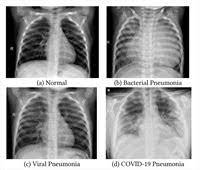

Pneumonia Dog Lung Cancer Xray / Canine Chronic Bronchitis A Review And Update Today S Veterinary Practice / Preconditioning rat with three lipid emulsions prior to acute lung injury affects cytokine production and cell apoptosis in the lung and liver.. The condition of your lungs. Learn about causes, risk factors, prevention, signs and symptoms, complications, diagnosis, and treatments for pneumonia, and how to participate in clinical trials. Some people also may develop pain in the chest wall. This growth can spread beyond the lung by the process of metastasis into nearby tissue or other parts of the body. Lung cancer, also known as lung carcinoma, is a malignant lung tumor characterized by uncontrolled cell growth in tissues of the lung.

Lung cancer is the top cause of cancer deaths in both men and women. Lung cancer begins in the lungs and may spread to lymph nodes or other organs in the body, such as the brain. Most cancers that start in the lung, known as primary. Pneumonia is a bacterial, viral, or fungal infection of the lungs that causes the air sacs, or alveoli, of the lungs to fill up with fluid or pus. What are the overlapping symptoms and outlook? Some people also may develop pain in the chest wall. Documents similar to pneumonia xray. Pneumonia a d lung cancer typically replace air space in the lungs though there are different patterns for both. More commonly, we see cancer. Lung cancer, also known as lung carcinoma, is a malignant lung tumor characterized by uncontrolled cell growth in tissues of the lung. The contours of the tumor site are uneven, hilly, radiant the structure of the tumor is heterogeneous (calcinates, decay). Acute pneumonias, acute viral respiratory infection. But this wasn't always the case.

Chronic bronchitis is a disease in dogs affecting the smaller airways that branch out from the trachea (windpipe). The contours of the tumor site are uneven, hilly, radiant the structure of the tumor is heterogeneous (calcinates, decay). Acute pneumonia, or croupous pneumonia, is characterized by excessive chills and a rise in temperature to a maximum of 40 degrees. Failure, pneumonia, allergic lung disease, and lung. Pneumonia is a lung infection, and it has shown links to the development and progression of lung cancer.

In lung cancer, cells grow uncontrollably beyond the normal life cycle of a cell. A new challenge for prevention and therapy. } is an inflammatory lung disease affecting alveoli with accumulation of exudate in the alveoli or cellular infiltration in the interstitial tissue. A dog affected by the second type of cancer skips a few phases and it can be diagnosed only after making a biopsy of the lung tissue, process which can be quite unpleasant for both the dog and its owner. A nationwide analysis in china.

Lung cancer, also known as lung carcinoma, is a malignant lung tumor characterized by uncontrolled cell growth in tissues of the lung. Acute pneumonias, acute viral respiratory infection. More commonly, we see cancer. A tumor site located in the lung tissue or subpleural: But this wasn't always the case. Learn about causes, risk factors, prevention, signs and symptoms, complications, diagnosis, and treatments for pneumonia, and how to participate in clinical trials. This growth can spread beyond the lung by the process of metastasis into nearby tissue or other parts of the body. Lung cancer is the top cause of cancer deaths in both men and women. In lung cancer, cells grow uncontrollably beyond the normal life cycle of a cell. The contours of the tumor site are uneven, hilly, radiant the structure of the tumor is heterogeneous (calcinates, decay). Metastatic lung cancers (cancers that spread to the lungs from other locations) are much more common in dogs than primary lung cancers. It is strongly tied to cigarette use. What are the overlapping symptoms and outlook?